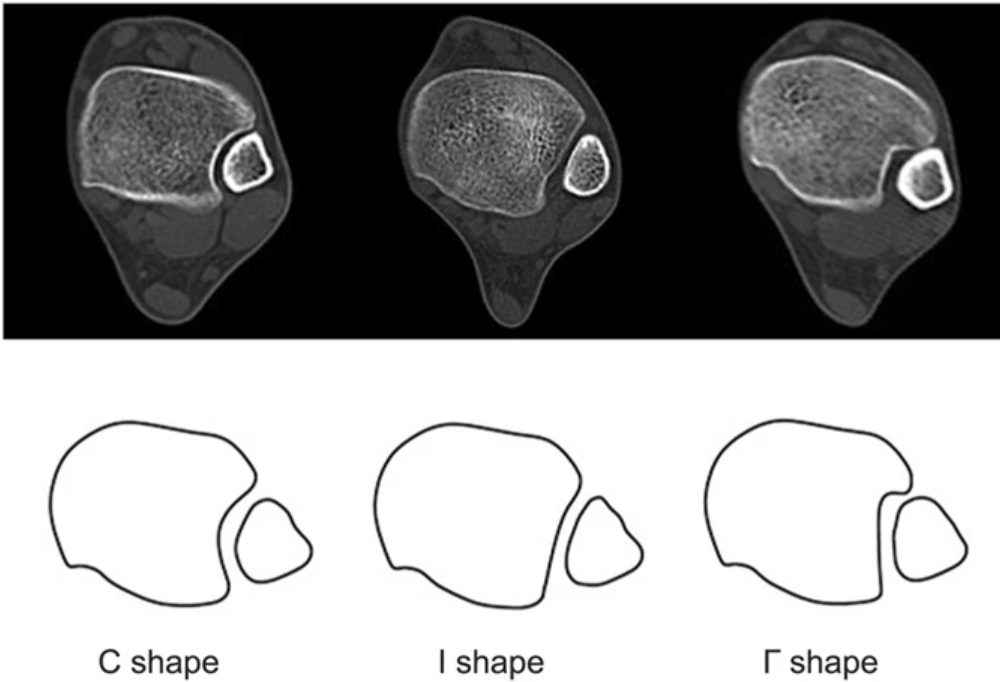

Костная конфигурация

Рис. 2. Варианты строения межберцового синдесмоза

Рис. 3. Суставная поверхность межберцового синдесмоза

Межберцовый синдесмоз образован двумя костями и четырьмя связками. Медиальная шероховатая выпуклая поверхность дистального отдела малоберцовой кости сочленяется с латеральной треугольной малоберцовой вырезкой дистального отдела большеберцовой кости (incisura tibialis), формируя фиброзное соединение.

Размер и форма вырезки большеберцовой кости играют важную роль в патологии голеностопного сустава. Мелкая вырезка может предрасполагать к рецидивирующим растяжениям или повреждениям синдесмоза с переломо-вывихами. Передний бугорок большеберцовой кости (бугорок Шапута, Chaput’s tubercle) крупнее заднего и препятствует смещению малоберцовой кости кпереди. Более скромный задний бугорок допускает смещение малоберцовой кости кзади. При переломах малоберцовой кости, вызванных наружной ротацией, задний бугорок выступает точкой опоры (fulcrum), вокруг которой дистальный отдел малоберцовой кости ротируется кнаружи вдоль своей продольной оси.